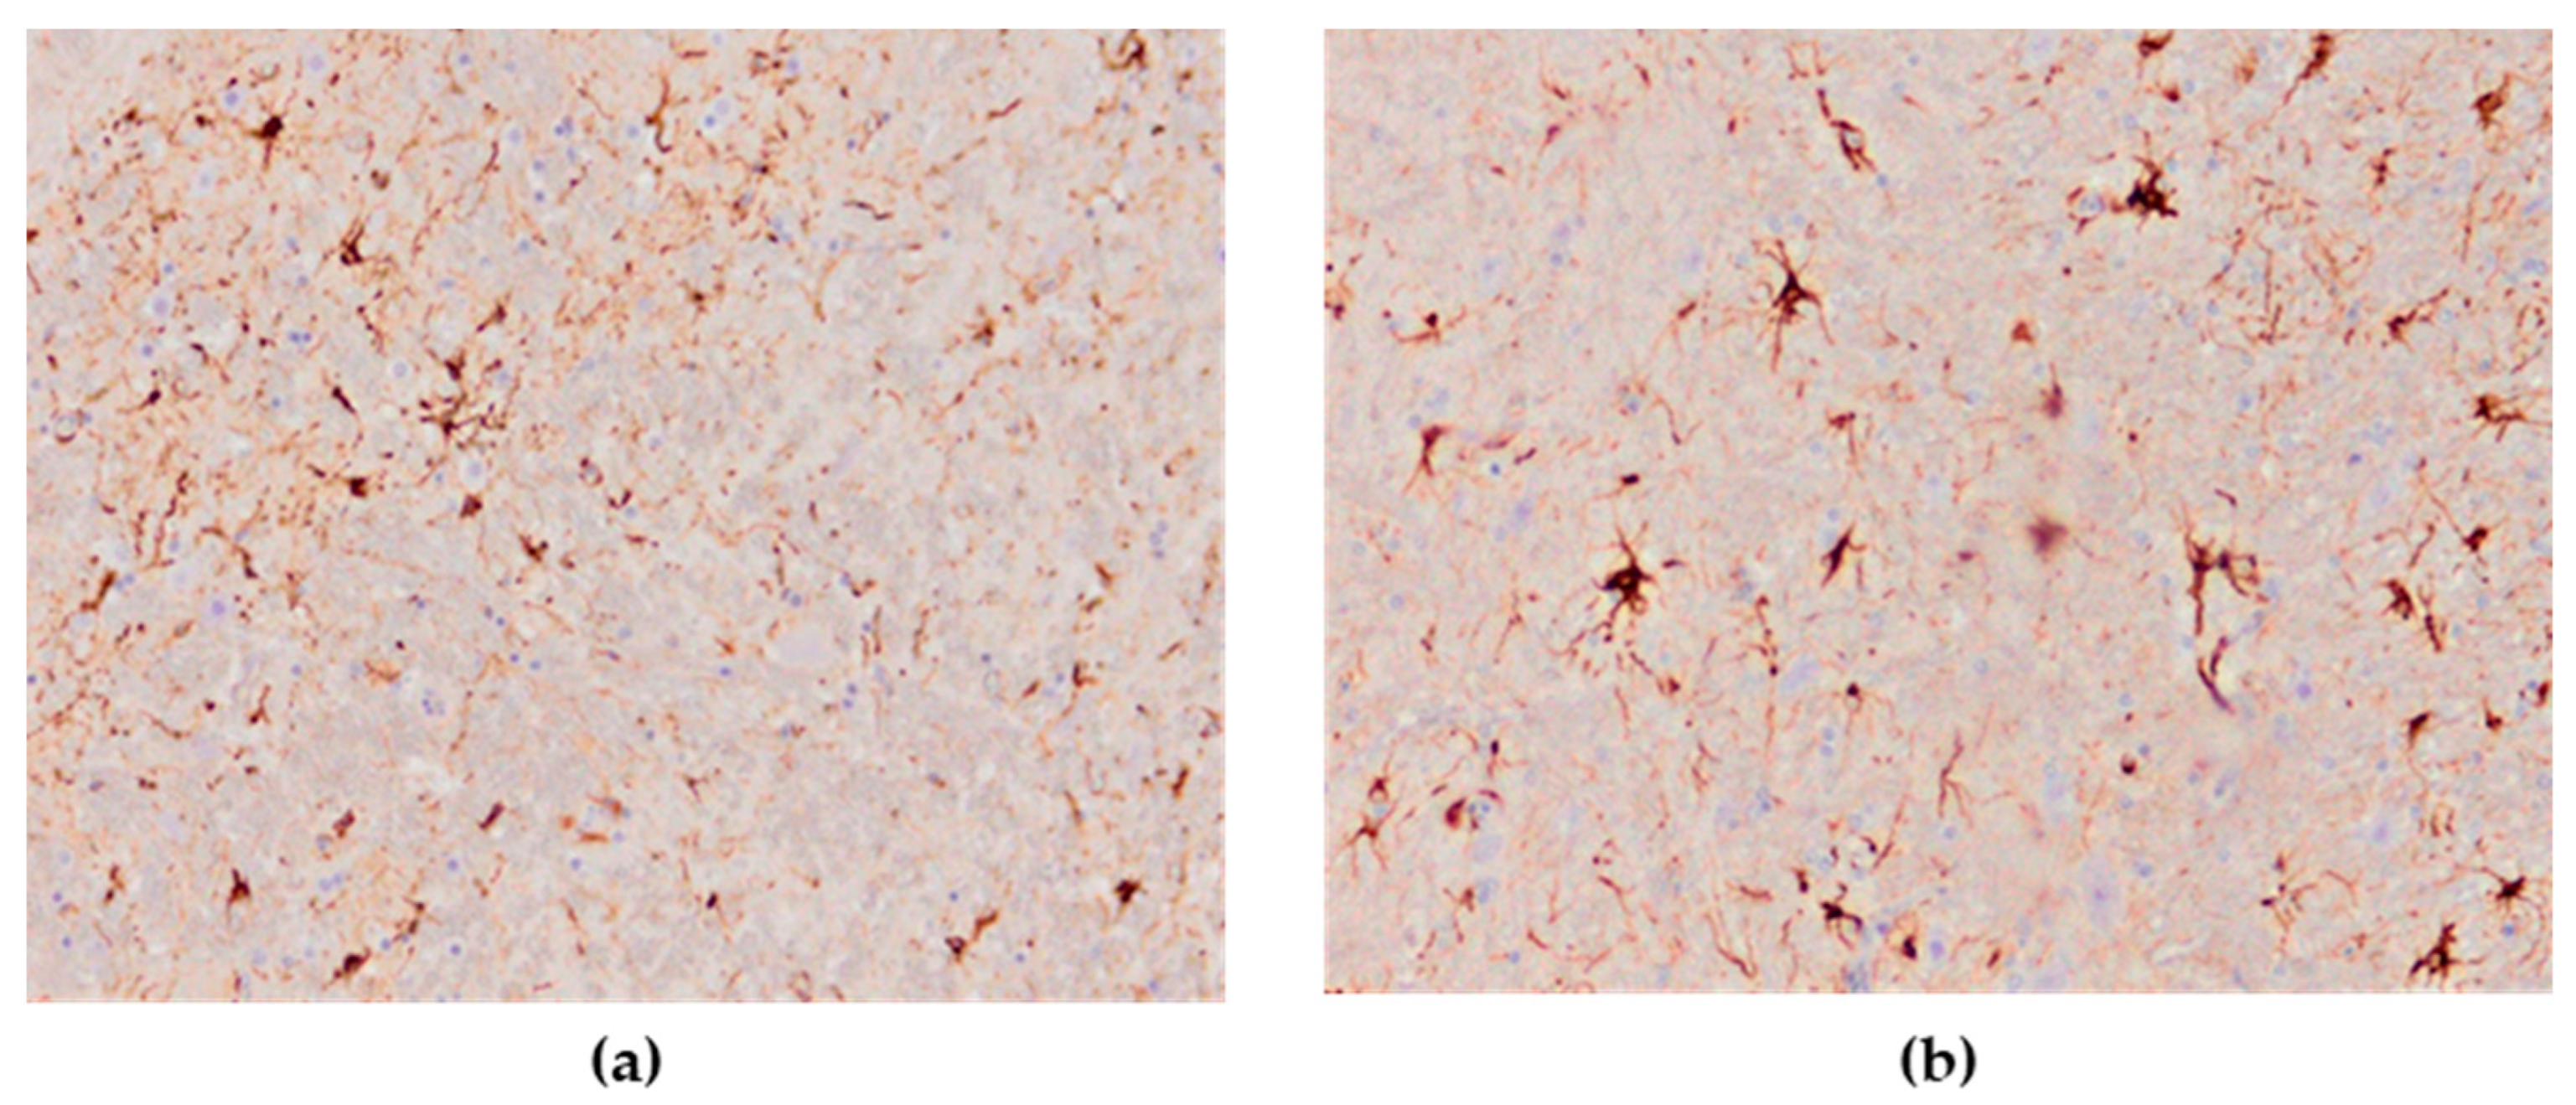

3.3.2. Astrocytes